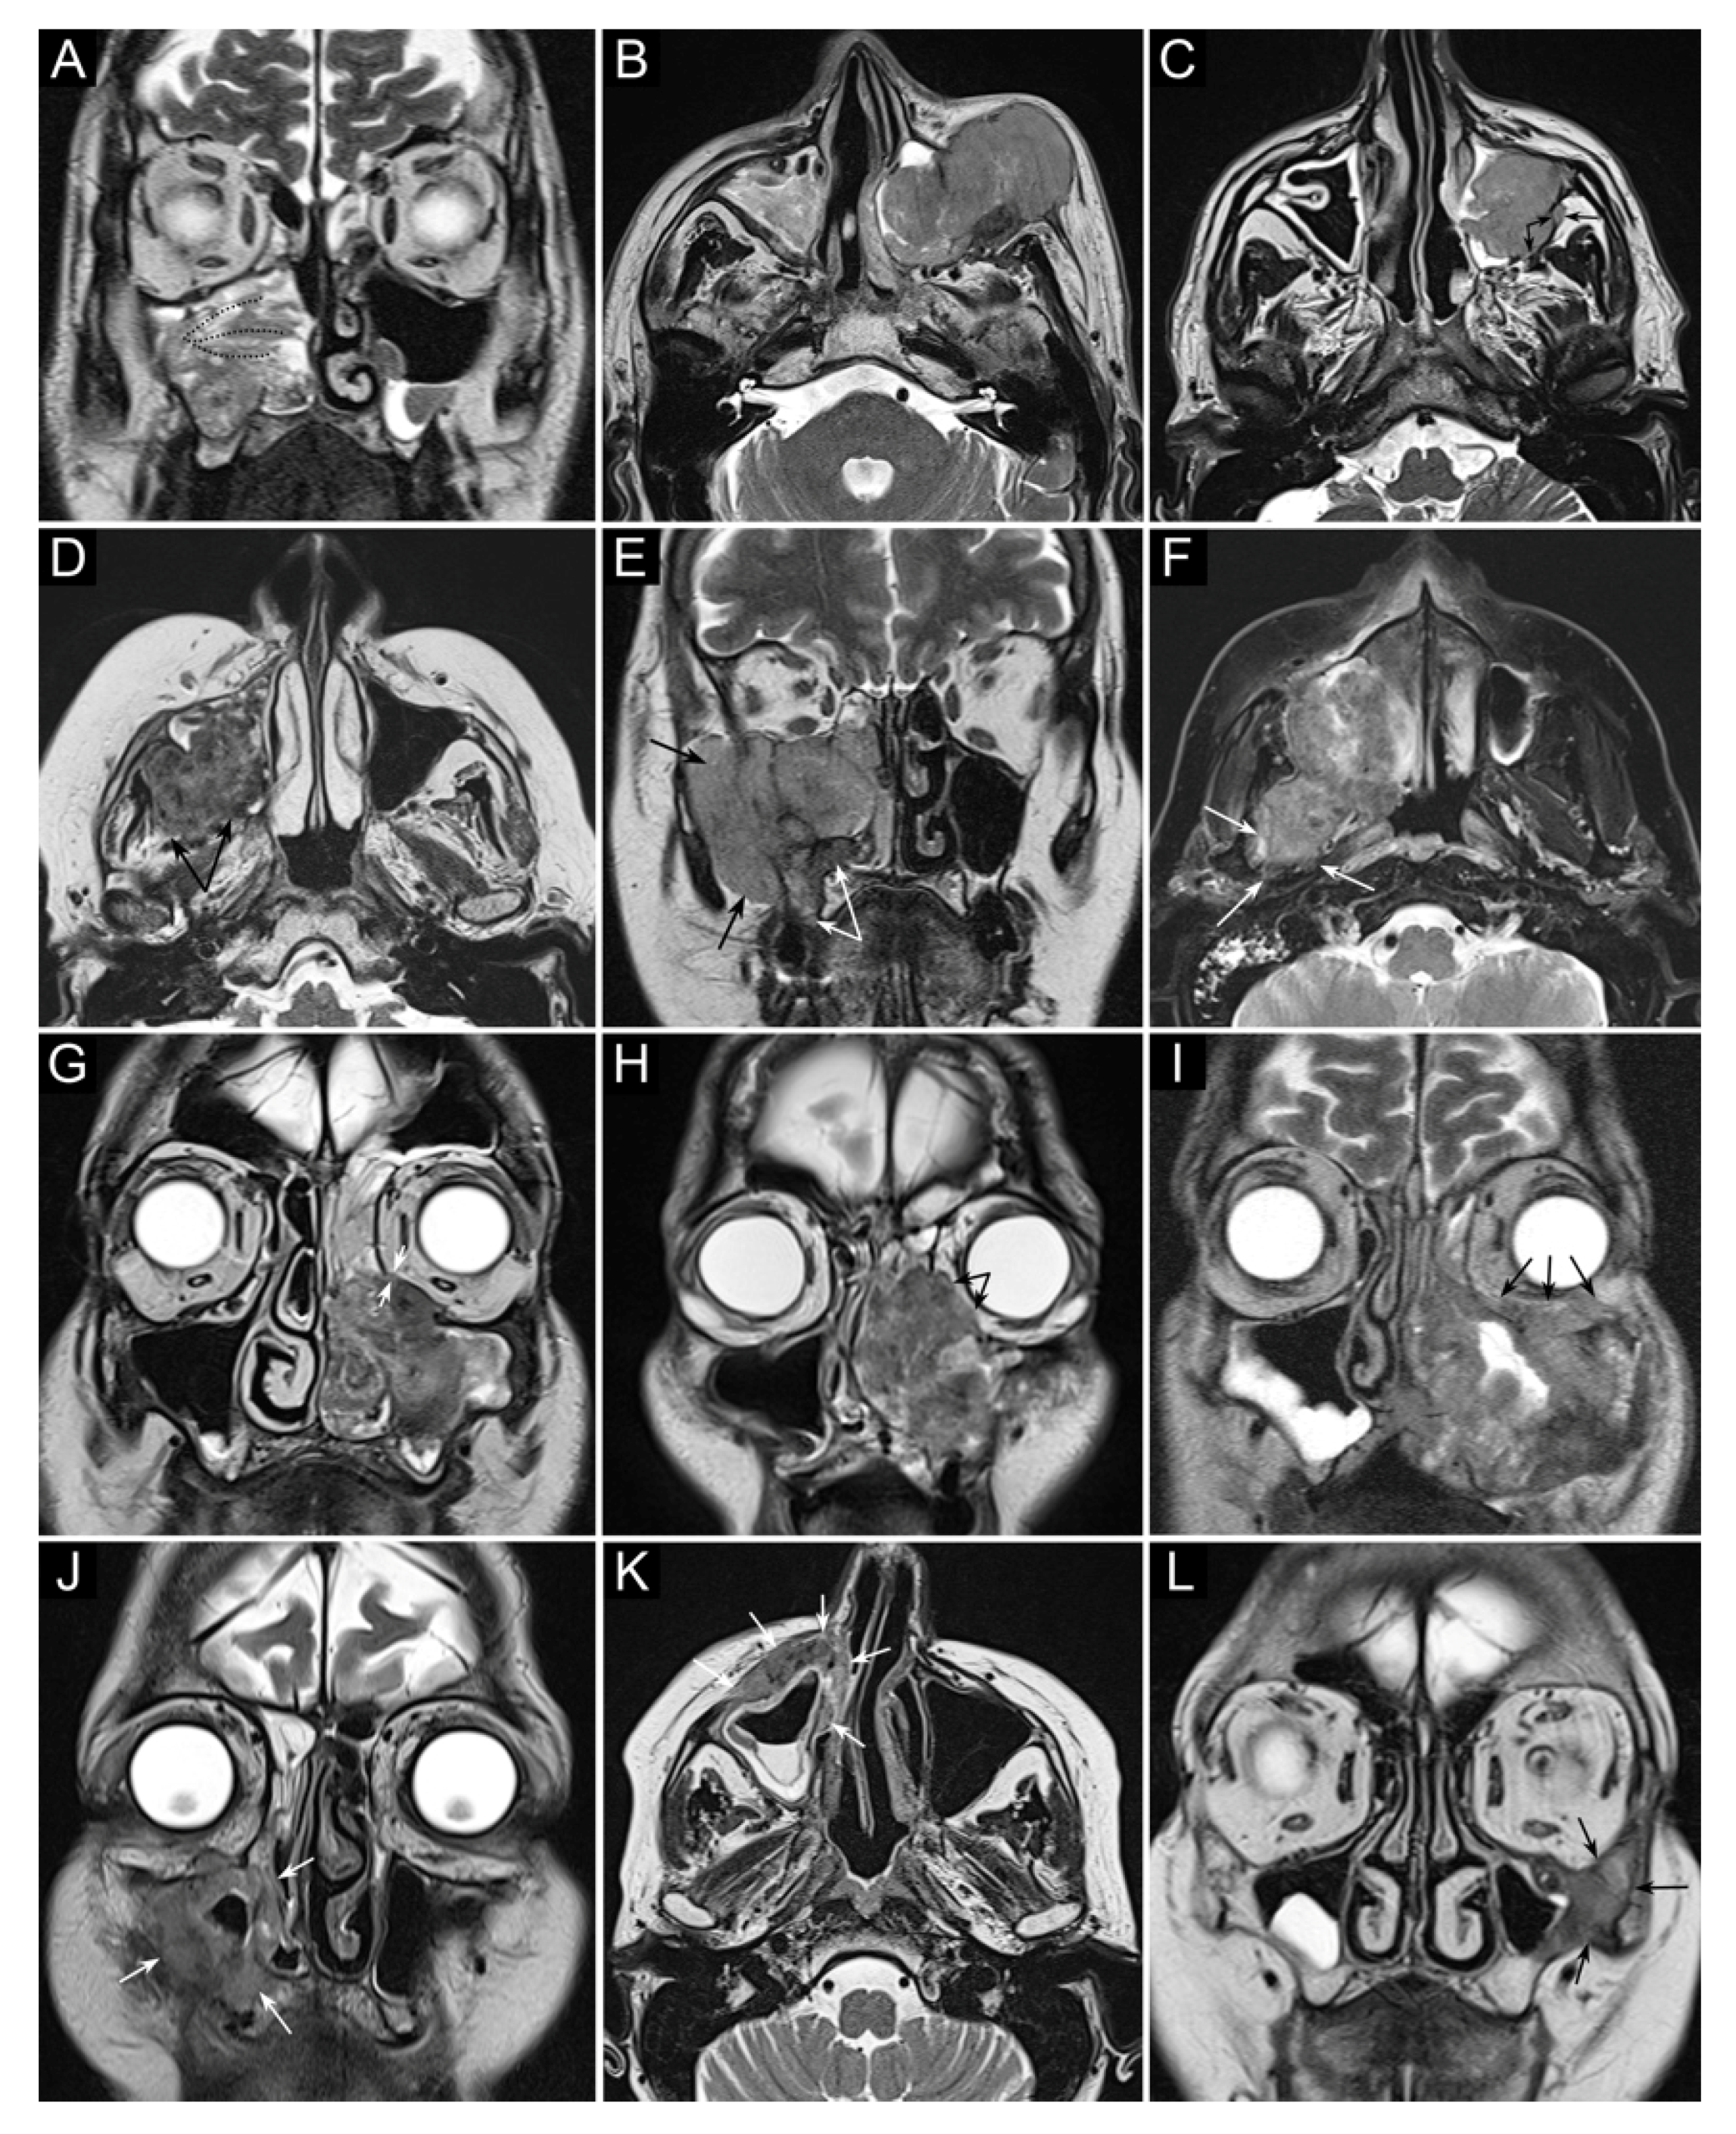

- Maroldi, R.; Borghesi, A.; Ravanelli, M.; Golemi, S.; Farina, D. The role of morphologic and functional imaging in pretreatment assessment. Adv. Otorhinolaryngol. 2020, 84, 28–45. [Google Scholar]

- Maroldi, R.; Farina, D.; Battaglia, G.; Maculotti, P.; Nicolai, P.; Chiesa, A. MR of malignant nasosinusal neoplasms frequently asked questions. Eur. J. Radiol. 1997, 24, 181–190. [Google Scholar] [CrossRef]